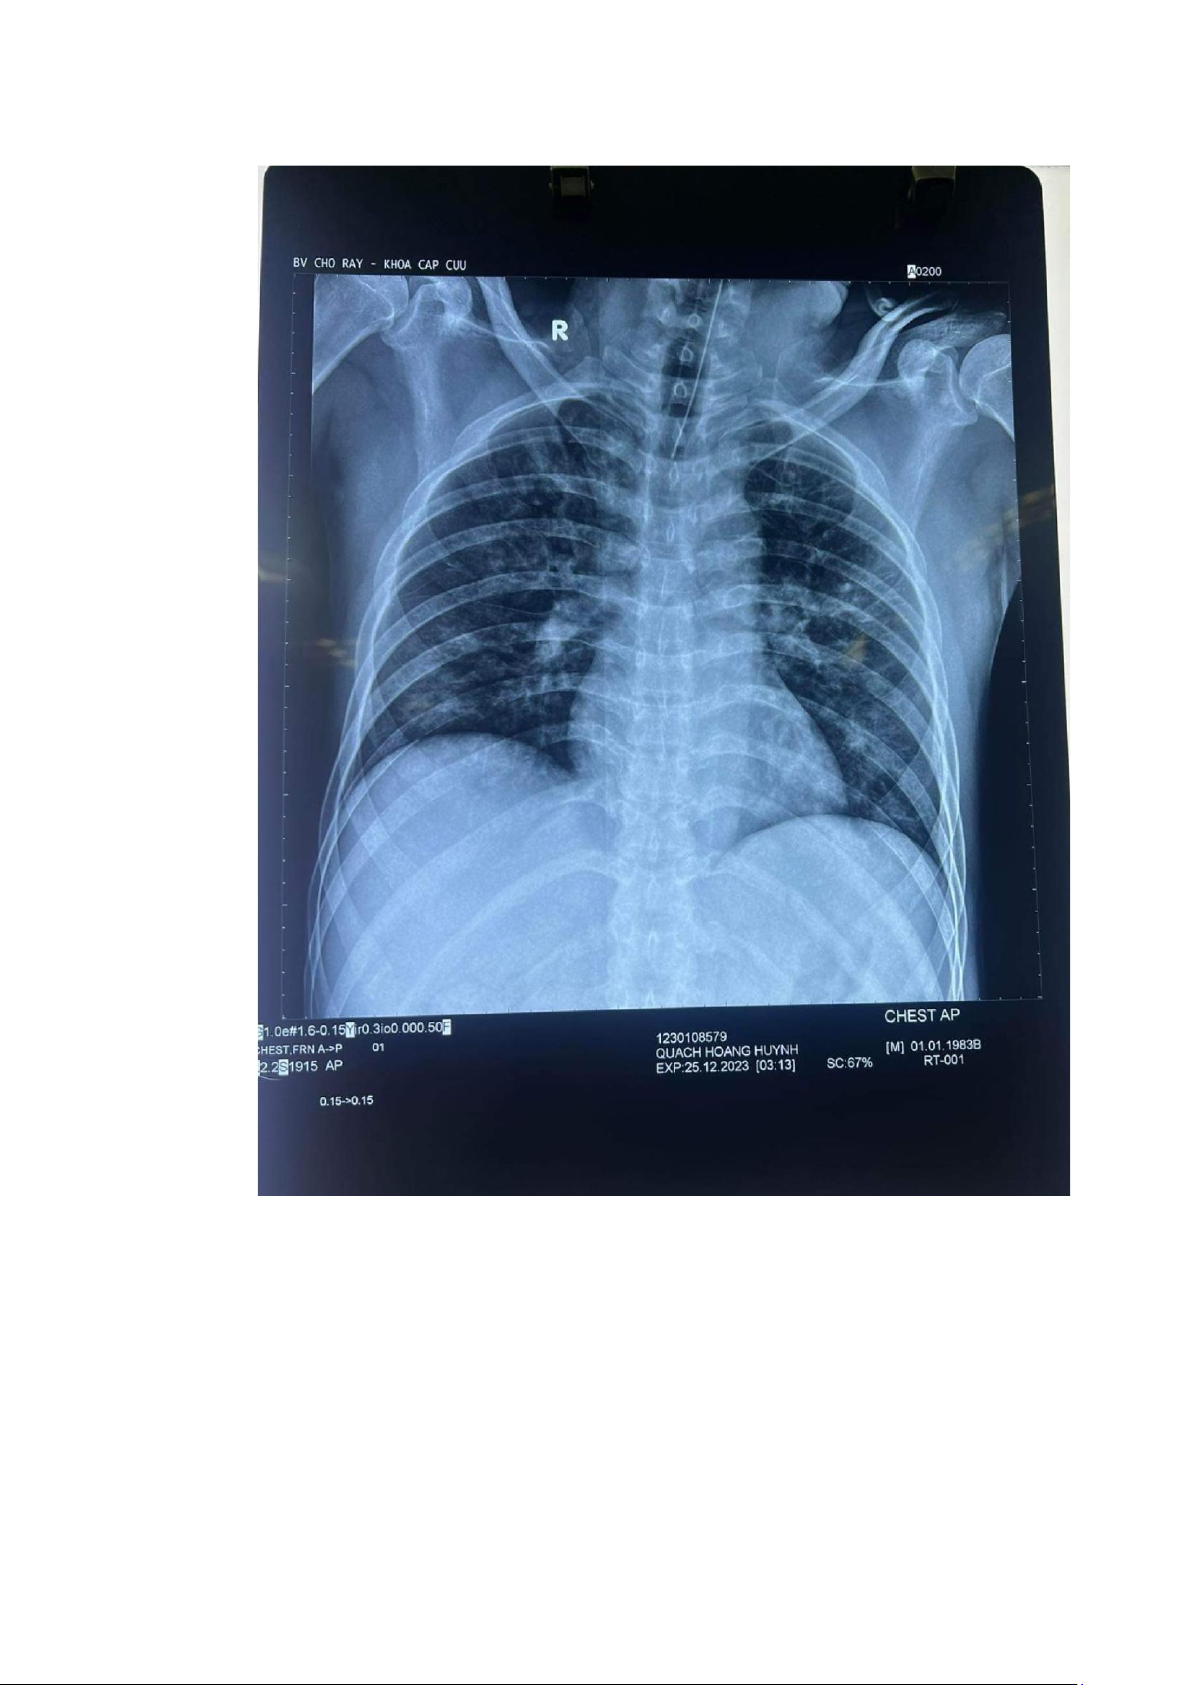

6. Xquang ngực thẳng 25.12.2023

Tổn thương phế nang dạng mô kẽ rải rác hai phổi, đặt NKQ đúng vị trí